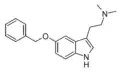

| 5-BT | artificial | 5-OCH2C6H5 | H | H | 5-Benzyloxytryptamine | 20776-45-8 |